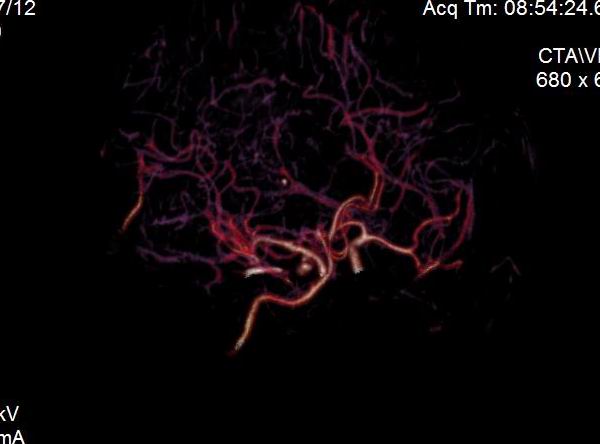

男.60岁,渐进性意识不清,ct检查双侧额颞顶部硬膜下血肿,开颅术后行脑血管cta,大脑中动脉起始部见一瘤状血管扩张。请各位老师留下宝贵意见

太常见了,报动脉瘤就可以

符合动脉瘤表现。

符合动脉瘤表现。

动脉瘤。

颅内动脉瘤。

后重建做得不是很好看,要将维蒂斯环充分显示,最好在增加一个mip。这样不好定位。

小动脉瘤

典型

符合动脉瘤的表现

动脉瘤

符合动脉瘤表现。

小动脉瘤

典型